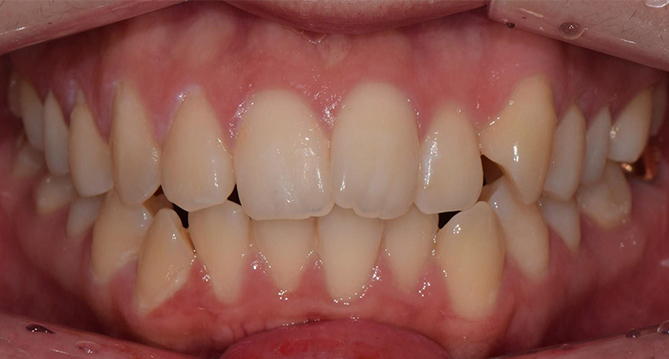

연세새빛치과 전체치아교정[클리피씨] 교정 전

연세새빛치과 전체치아교정[클리피씨] 교정 후